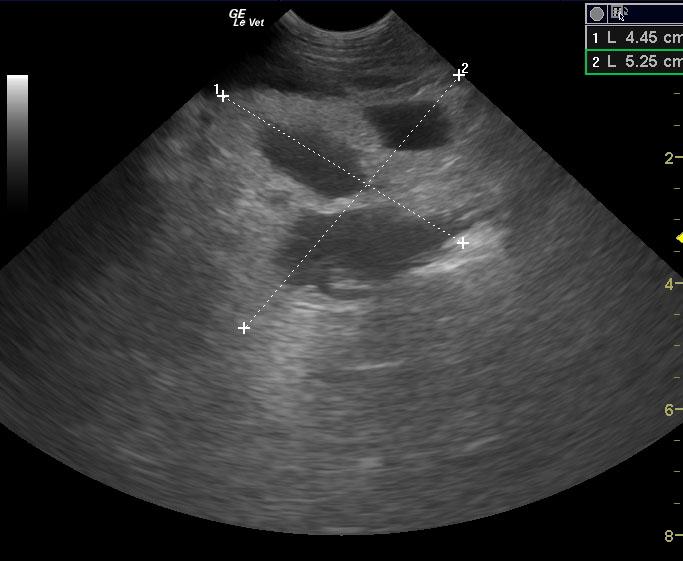

Extensive mixed hypoechoic pancreatic parenchyma is noted much of which lacks blood flow on power Doppler assessment. Gastroduodenal thickening is noted with duodenal spasm. Cavitations are noted in the pancreas with echogenic fluid. Extensive hyperechoic fat is noted.